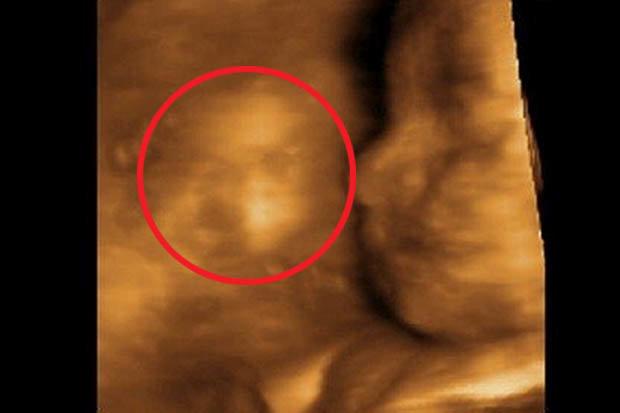

Doar că, odată ajunsă la doctor, femeia a trăit un adevărat șoc! Când a privit mai atentă ecografie 4D dată de specialist, Jane a observat un semn!

Mai exact, în imagine a putut vedea clar chipul unui al doilea copil, deși medicii au confirmat că are doar unul în uter.

Femeia de 34 de ani și-a dat atunci seama despre ce este vorba! În urmă cu 12 ani a pierdut prima sarcină în urma unui avort și acum, gravida consideră că ceea ce a văzut pe ecografie este de fapt spiritul copilului pierdut, ce parcă încearcă să arate că va veghea asupra noii sarcini.